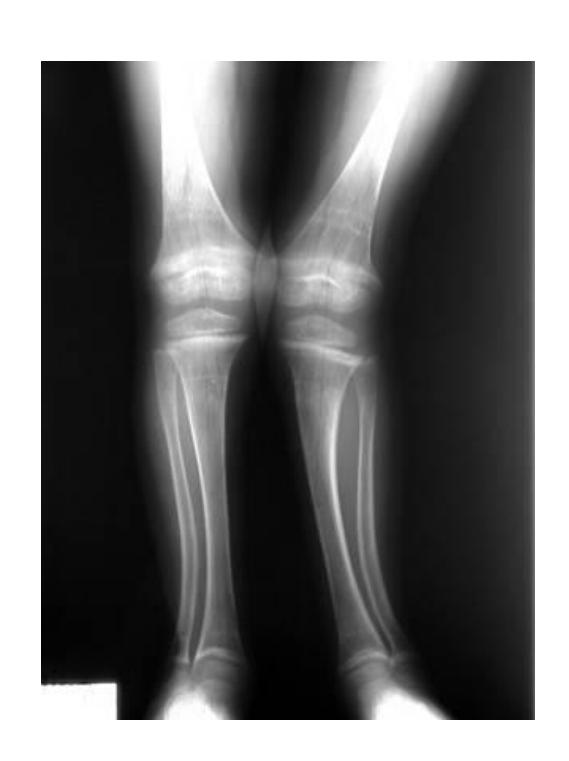

Genu Valgum

Q1: What do you see in this image?

- A. Genu valgum, Coronal view

A 60-year-old overweight lady presented to clinic with chronic pain in both knees. A standing AP x-ray of both knees is shown.

Q1: Mention TWO findings on this X-ray

- Narrowing of the joint space

- Osteophytes

Q2: What is the diagnosis?

- Bilateral knee osteoarthritis